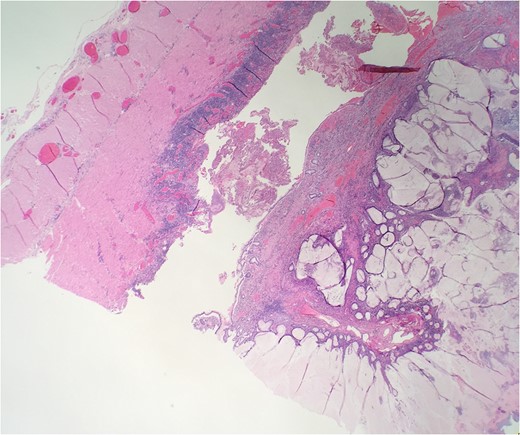

Over the course of 12 days, the patient failed conservative management of large bowel obstruction, and subsequently underwent laparoscopic extended right hemi colectomy with primary anastomosis. On gross examination the transverse colon was firm, wall was thickened and proximal portion was severely dilated (Fig. 1). The specimen had massive inflammatory polyposis and colitis cystica profunda complicating idiopathic IBD, indeterminate type (Fig. 2). There was evidently continuous involvement of a long segment of the proximal colon with transmural chronic inflammation, fissuring ulcerations and chronic subserositis, which combined to produce mural thickening, rigidity and obstructive dilation of the cecum and ileum. Ileum was unremarkable. Microscopic examination the mass revealed colonic mucosa with extensive hyperplastic changes, mild active chronic colitis and crypt micro abscess without dysplasia (Fig. 3). The distal colonic margins demonstrated paneth cell metaplasia indicating IBD extends distally beyond the region of polyposis and may ultimately prove to be ulcerative colitis (UC).

Microscopic examination reveals extensive hyperplastic changes with mucinous pool.